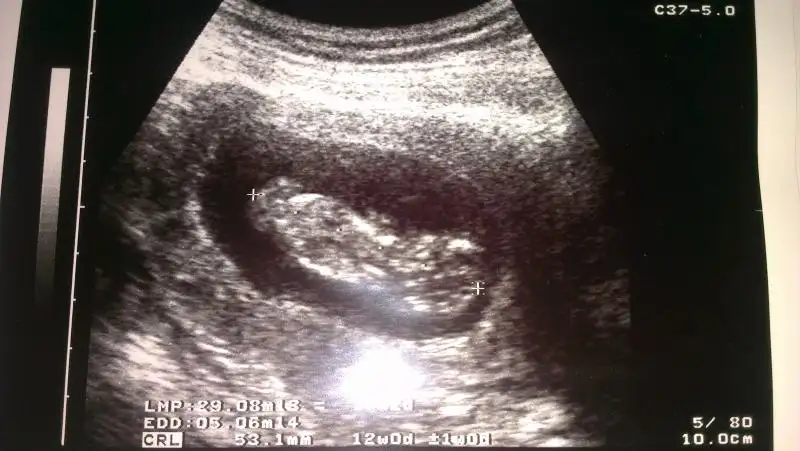

Eki Görüntüle 867635 Eki Görüntüle 867636 Eki Görüntüle 867638

cinsiyeti ne olabilir nubu göremedim ben

Cok baktim ama ultrasonun goruntu kalitesi dusuk canim ya gorunmuyor hic doktor bi tahminde bulunmadimi